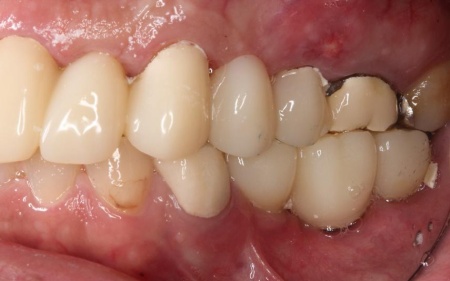

次に、右上奥歯と前歯にインプラント治療を行いました。

右上奥歯は、歯周病でインプラントを埋入するために必要な骨が不足していたため、上顎の奥にある上顎洞の底を押し上げて人工の骨を補う「サイナスリフト」という骨造成を併用しています。

右上前歯も同様に骨が少なかったため、こちらは骨の移植を行って骨量を確保したのち、インプラントを埋入しました。

インプラントが骨にしっかりとなじんだことを確認したら、白くて強度の高い人工歯「ジルコニアクラウン」を装着しました。

他院で治療を行った左下奥歯3本のインプラントは、土台をそのまま活かして人工歯だけ作り直し、噛み合わせを調整します。

左下奥歯1本、右下奥歯2本に装着されていた古い被せ物はすべて外し、ジルコニアクラウンと交換しました。